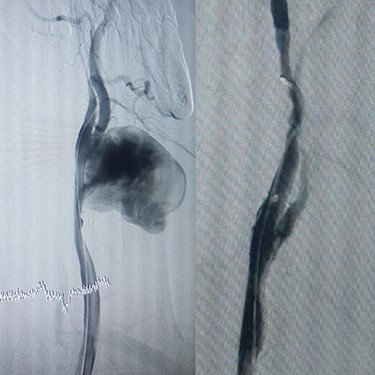

Case 3 – A 44-year-old man, known case of BD, who underwent open surgery for right common iliac artery aneurysm 1 year ago. The patient was referred to our hospital with a huge pulsatile neck mass. The right femoral artery pulse was absent in physical examination. CTA showed the iliac graft was thrombosed, but his lower limb did not have symptoms of ischemia. Corticosteroid therapy was prescribed before starting the procedure. In addition, a left carotid artery aneurysm was identified (Fig. 4A), so a stent-graft was inserted in the left common carotid (Fig. 4B). The pulsation and bruit of the mass disappeared immediately after the procedure and patient was discharged without complications. After 1-year follow-up, there was no sign of pseudo-aneurysm and the stent-graft was open.

(A) Carotid angiography before stent-graft placement (left), (B) after stent-graft placement (right).